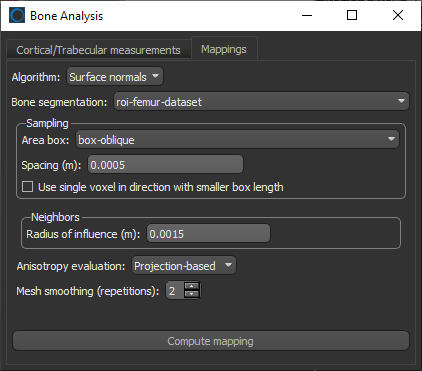

- Do the following on the Mappings tab:

- Choose Surface normals in the Algorithm drop-down menu.

- Choose the region of interest that you created for this tutorial in the Bone segmentation drop-down menu.

- Choose the box that encloses the area that you want to include in your analysis in the Area box drop-down menu.

- Enter a value of 0.002 m in the Spacing edit box.

NOTE Although the highest resolution, or lowest spacing, of the tutorial dataset is 0.5 mm, this should be increased to 2.0 mm if the entire 3D shape of the femur will be mapped.

- Select a value between 1 and 3 mm in the Radius of influence edit box.

NOTE The radius of influence defines the kernel size, or elementary volume, within which anisotropy will be evaluated. You should note that a too small radius of influence may result in a low signal-to-noise ratio, while a too high radius can result in averaging and edge effects.

- Choose Projection-based in the Anisotropy drop-down menu.

- Choose a number of iterations in the Mesh smoothing (repetitions) spin box, optional.

- Click the Compute Mapping button.